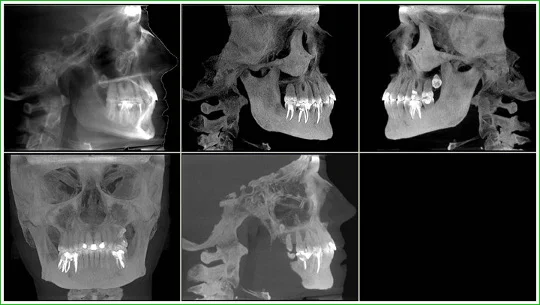

Снимок зубов 3D

Если вы пришли к ортодонту, челюстно-лицевому хирургу, имплантологу или даже пластическому хирургу на консультацию, скорее всего,одним из его первых назначений будет сделать компьютерную томографию (КТ) челюсти, или снимок зубов 3Д. Это современная и очень точная методика диагностики, позволяющая врачу посмотреть изображение челюсти пациента под любым углом и в любой проекции, причем даже тогда, когда пациент уже покинул его кабинет.КТ, в отличие от ортопантомограммы,дает объемное изображение челюсти без искажений и позволяет заглянуть в любой слой тканей, сделав своеобразный виртуальный срез, без необходимости вживую проводить пациенту лишние травматичные процедуры. Эффективность и безопасность диагностики и лечения, таким образом, значительно повышаются.

Стоматологический компьютерный томограф похож на ортопантомограф. Во время процедуры пациент стоит или — в особых случаях — сидит. На шею и грудь надевают защитный фартук со свинцовой прослойкой. Пациент зубами сдавливает специальную накусочную пластину, лбом упирается в фиксирующую опору, а руками держится за ручки. Это позволяет ему занять правильное положение и замереть на 14 — 24 секунды, в зависимости от выбранного режима и частоты съемки. Именно столько времени необходимо, чтобы плоскостной сенсор томографа сделал один оборот вокруг головы пациента. За это время датчик успевает сделать около 200 снимков в разных проекционных срезах. Обработка данных и построение 3D-модели занимает еще несколько минут, плюс запись томограммы на диск — и через 10 — 15 минут точнейшая информация о состоянии вашей зубочелюстной системы у вас в руках.